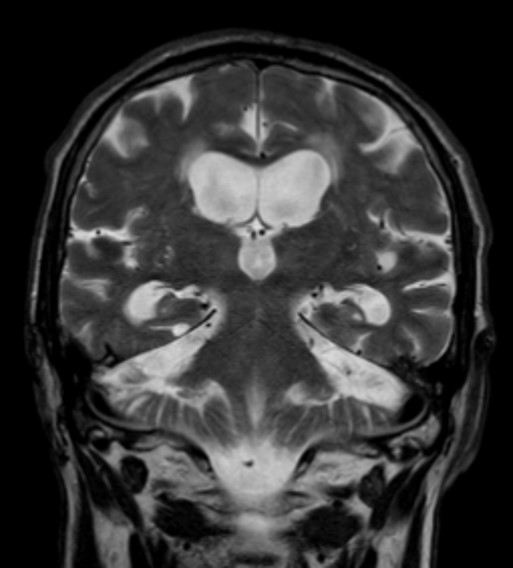

Method: The CT found the haemorrhage in right parahippocampal gyrus area. The MRI found signs of triventricular hydrocephalia.

Triventricular hydrocephalia on MRI